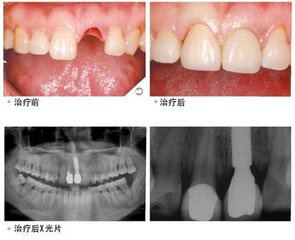

广州越秀圣贝口腔门诊部连锁牙科连锁机构的指出,如果牙齿必须要拔除,则需要等到拔牙创口完全愈合以后,才能进行准确的牙齿扫描从而制作正式的假牙。

拔牙创口的完全愈合需要有一个过程。在正常的情况下,拔牙后在牙床上会留下一个很深的创口,里面充满了血凝块,。过后会慢慢长出修复性肉芽组织,逐渐填满这个创口,并逐渐长平,直到创口完全愈合,拔牙创口的骨头需要3个月才能基本长好。拔牙后,必要时可先做临时假牙,可以进行正常的牙齿咀嚼和说话。假牙用什么材料好?

拔牙以后,牙齿修复的较佳时间是三个月到半年,并不是每个人拔完牙2-3个月就一定能装假牙的,有的人因为拔牙时损伤较大或者组织修复很慢,3个月创口还是愈合不好,等待的时间可能要更长一些;还有的人缺牙处牙槽骨高低不平,甚至存在骨突和骨尖,那么还需要进行牙槽骨修整手术,特别是全口拔牙后的病员常常会碰到此类问题。

广州越秀圣贝口腔门诊部连锁采用目前先进的种植之一。耐用持久,世界上颗种植牙已正常使用40年。运用广泛,适用于牙齿缺损、牙列缺损、全口无牙。品 质坚硬,基台坚固,稳定性强,大限度恢复正常咀嚼功能,咬合力达到正常牙的98.98%;生物相容性极好,口感良好,无任何异物感,临床适应症高于 98.98%,不良反应低于0.02%;美学效果良好,大限度还原真牙形态;定位准确,无其他损伤,种植体直接嵌入牙槽骨,不损伤相邻牙齿; 有效防止牙齿缺失后牙槽骨继续萎缩。经过一段时间后,种植体就会与周围的骨组织发生骨结合,并为牙齿修复体如牙冠、固定桥、部分活动义齿或全口义齿提供坚固的固位力。